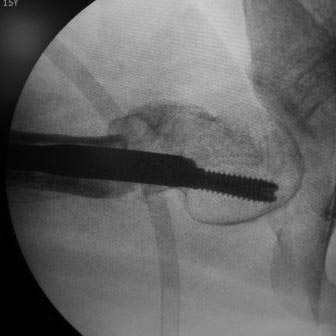

Уважаемые коллеги. Больная оперирована 06.03.15г клинок был сломан, и пока его с трудом удалили, от неполноценного вертела почти ничего не осталось, сломанный шуруп тоже удален, шейка совсем короткая, , ШДУ около 95гр, из-за сильного остеопороза при сверление в положении чуть вальгуса наружная стенка крошится , и еще что интересно при первой операции головка бедра оказалось фиксирована в положении ретроверсии примерно 10-15 гр.. и с трудом удалось выпрямить головку и шейку до 0 гр. , укорочение было чуть больше 1см , п/о -2см, пока фиксация - гипсовый сапожок с деротатором. Дальше как быть? Может временно фиксировать кокситной повязкой( канда каст)?